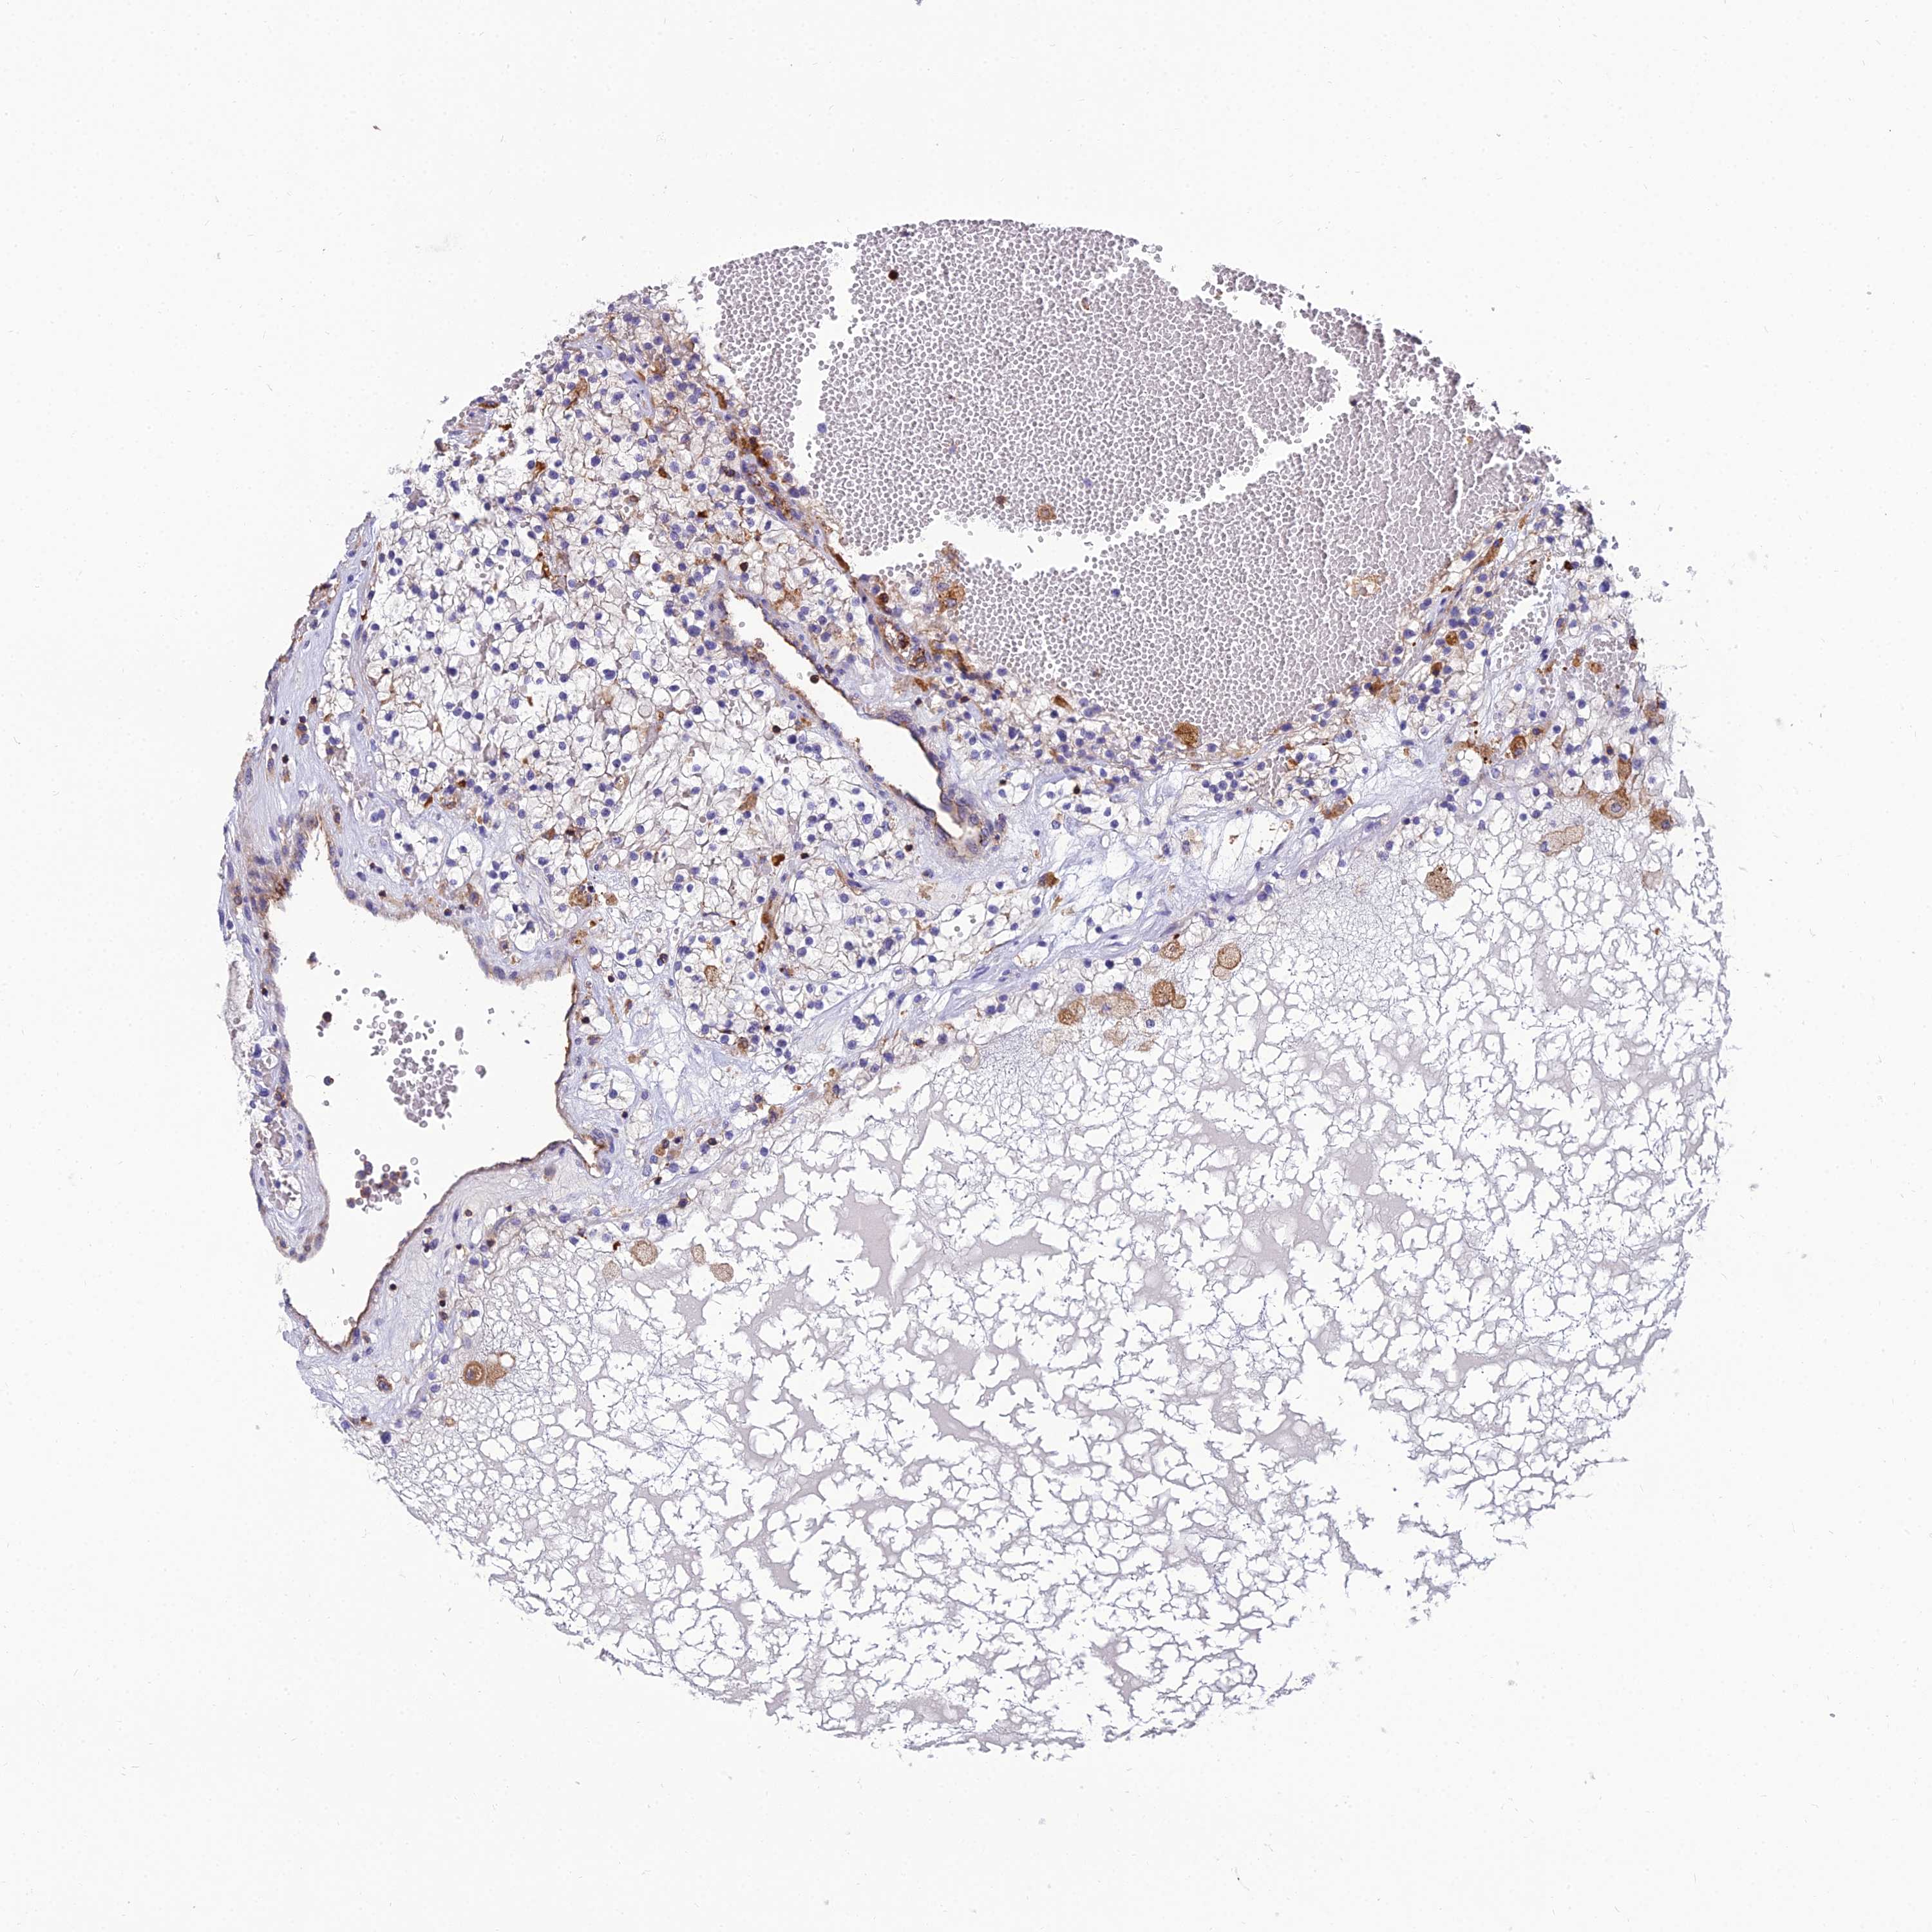

KIDNEY RENAL CLEAR CELL CARCINOMA (VALIDATION) - Interactive survival scatter ploti

The Survival Scatter plot shows the clinical status (i.e. dead or alive) for all individuals in the patient cohort, based on the same data that underlies the corresponding Kaplan-Meier plots. Patients that are alive at last time for follow-up are shown in blue and patients who have died during the study are shown in red.

The x-axis shows the expression levels (FPKM) of the investigated gene in the tumor tissue at the time of diagnosis. The y-axis shows the follow-up time after diagnosis (years). Both axes are complimented with kernel density curves demonstrating the data density over the axes. The top density plot shows the expression levels (FPKM) distribution among dead (red) and alive patients (blue). The right density plot shows the data density of the survived years of dead patients with high and low expression levels respectively, stratified using the cutoff indicated by the vertical dashed line through the Survival Scatter plot. This cutoff is automatically defined based on the FPKM cutoff that minimizes the p-score. The cutoff can be changed by dragging the vertical line or by entering a cutoff value in the square labeled "Current cut-off".

Under the Survival Scatter plot the p-score landscape (black curve; left axis) is shown together with dead median separation (red curve; right axis). Dead median separation is the difference in median mRNA expression between patients who have died with high and low expression, respectively. It is calculated as follows: median FPKM expression of dead patients with high expression - median FPKM expression of dead patients with low expression. This is intended to aid the user in visually exploring custom cutoffs and the associated p-scores and dead median separation.

Individual patient data is displayed and can be filtered by clicking on one or more of the category buttons on the top of the page. Categories describing expression level and patient information include: high, low, alive, dead, female, male and tumor stages. The scale of the x-axis can be toggled between linear and log-scale by clicking on the "x log" button. Mouse-over function shows TCGA ID, patient information and mRNA expression (FPKM) for each patient.

& Survival analysisi

Kaplan-Meier plots summarize results from analysis of correlation between mRNA expression level and patient survival. Patients were divided based on level of expression into one of the two groups "low" (under cut off) or "high" (over cut off). X-axis shows time for survival (years) and y-axis shows the probability of survival, where 1.0 corresponds to 100 percent.

PPP1R18 is not prognostic in Kidney Renal Clear Cell Carcinoma (validation)

Best expression cut offi

Based on the FPKM value of each gene, patients were classified into two groups and association between prognosis (survival) and gene expression (FPKM) was examined. The best expression cut-off refers the FPKM value that yields maximal difference with regard to survival between the two groups at the lowest log-rank P-value. Best expression cut-off was selected based on survival analysis .

When clicking on this number, the vertical dashed line indicating cut-off, the interactive survival plot, and the Kaplan-Meier curve will be adjusted to show results based on the best expression cut-off.

: 31.72

P scorei

Log-rank P value for Kaplan-Meier plot showing results from analysis of correlation between mRNA expression level and patient survival.

N/A

TCGA RNA samplesi

RNA-seq data is reported as average FPKM (number Fragments Per Kilobase of exon per Million reads), generated by the The Cancer Genome Atlas (TCGA) .

Normal distribution across the dataset is visualized with box plots, shown as median and 25th and 75th percentiles. Points are displayed as outliers if they are above or below 1.5 times the interquartile range. FPKM values of the individual samples are presented next to the box plot.

Average pTPM 33.9

Number of samples 100